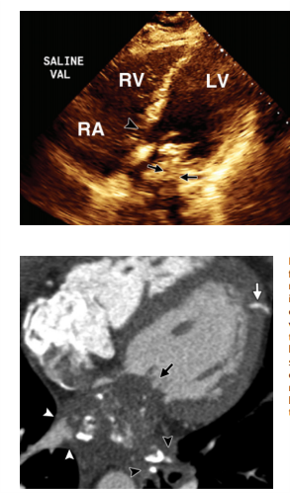

Ebstein anomaly